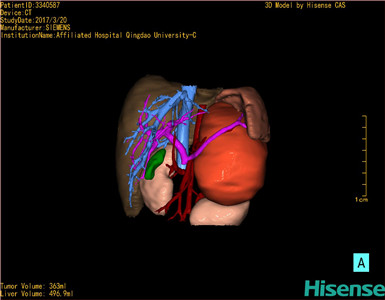

将0.625mm双源薄层CT资料的静脉期和动脉期Dicom格式文件导入海信CAS系统。

通过调节窗宽窗位调整CT序号,对肿瘤,肝实质,胆囊,下腔静脉,肿瘤,肝动脉、门静脉及肝静脉等进行三维重建;系统自动计算肿瘤体积和肝脏体积。

模拟手术操作,自动计算切除肿瘤体积。肝脏体积为496.9ml,肾上腺肿瘤体积363ml,术前规划手术方案,进行手术。

术前三维重建:

重建图片